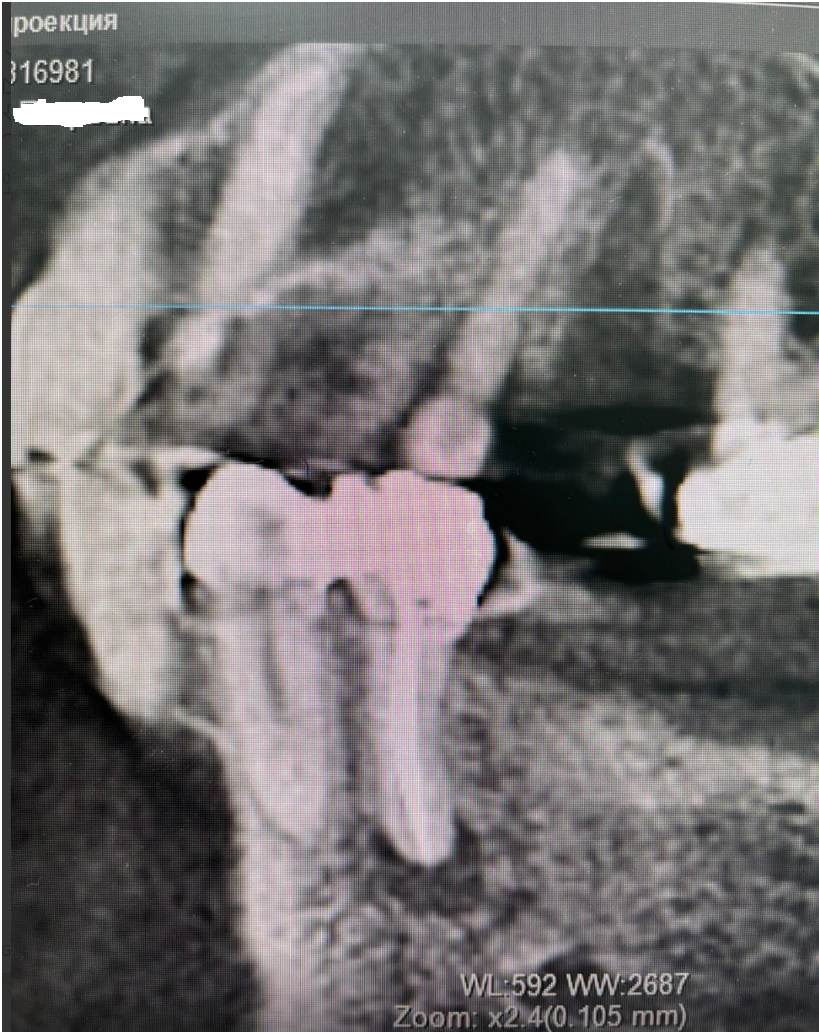

Женщина 74 года. Установила бюгельный протез на нижнюю челюсть 2 года назад, который крепится справа на коронке с замком, а слева на заглушенных имплантатах. Имплантатам свыше 15 лет, на консультациях сказали, что их больше нельзя использовать для протезирования, кость плохая, только удаление. Ортопед принял решение имплантаты не удалять, а использовать их в систему для бюгельного протеза. Недавно под протезом стал побаливать зуб при надкусывании. Сделала КТ. Справа на зубе под коронкой с замком, на котором держится эта конструкция, образовалась гранулема. Теперь встал вопрос: как быть. Почему образовалась гранулема? До протезирования ничего не было, могла такая конструкция вызвать воспаление? Можно ли вылечить данный зуб? В клинике, где делали КТ, предложили, как вариант, высверлить в коронке дырку и попытаться пролечить зуб.  Поможет ли это? Или снимать коронку, как полагается, и лечить классическим методом? Что можно сделать в данном случае? Или уже ничего не поможет? Оставить всё как есть до тех пор, пока зуб окончательно не разболится и просто его удалить?